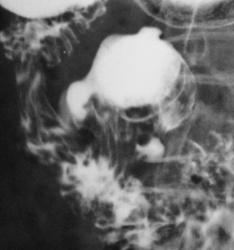

А там не один дивертикул в дивертикуле, а целых три.

2) По 1 снимку можно предположить, что самый дистальный дивертикул исходит не из крупного, а судя по шейке дивертикула из подковы 12-перстной кишки (хотя это не принципиально).

Шейка одна - и дивертикул один, а уж форма его, дело другое.

1) Прекрасное качество R-грамм, контраст Entero-Vu, в данном случае и не нужен.